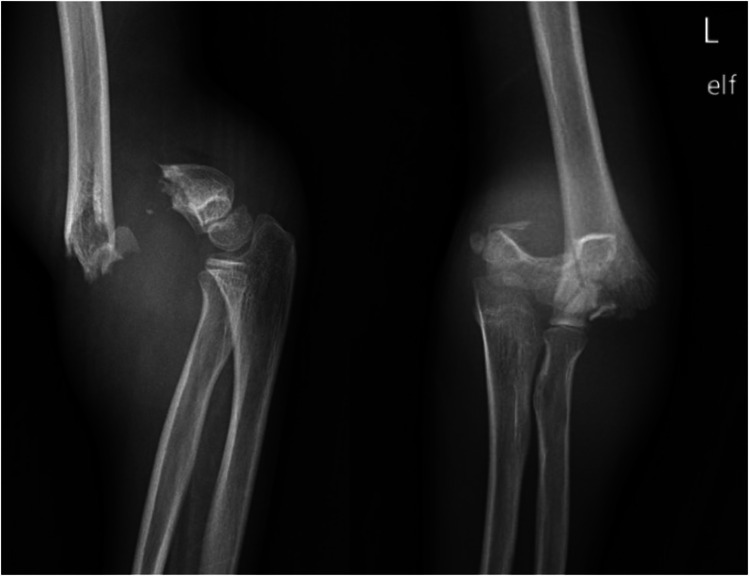

综述目的:本综述旨在全面分析小儿Gartland II型骨折的非手术治疗。最近发现:肱骨髁上骨折(SCF)是儿童人群中最常见的创伤性骨折之一,其特征是肱骨远端内侧柱和外侧柱之间的横向骨折。早期研究强烈反对将闭合复位和铸造作为Gartland II型骨折可接受的治疗方式,因为早期病例系列显示并发症发生率高;然而,最近的研究表明效果更好。Gartland II型髁上骨折的最佳治疗方法尚未完全阐明。本文综述了Gartland II型肱骨髁上骨折非手术治疗的适应症、并发症和结果。此外,它表明需要进一步的研究来指导管理这种情况。

Recent findings: Supracondylar humeral fractures (SCF) are one of the most common traumatic fractures in pediatric populations, characterized as transverse fractures at the distal humerus between the medial and lateral columns. Early studies strongly opposed closed reduction and casting as an acceptable treatment modality for Gartland type II fractures as an early case series showed high rates of complications; however, more recent studies have suggested better outcomes. The optimal management of Gartland Type II supracondylar fractures has yet to be fully elucidated. This review highlights the indications, complications, and outcomes of nonoperative Gartland Type II supracondylar humeral fracture management. Additionally, it demonstrates the need for further research to inform guidelines on managing this condition.